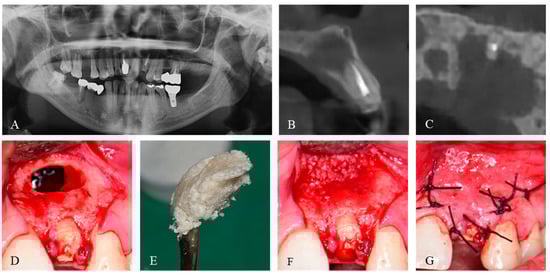

2. Case Presentation